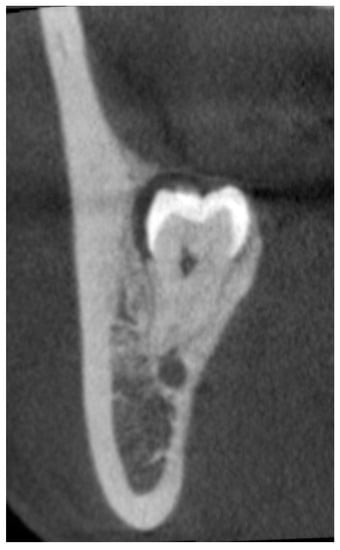

It is known that third molar impaction affects the periodontal health of the adjacent second molar and leads to periodontal attachment loss of the tooth [78]. It is caused by persistent infection because of food trapping and plaque retention, which leads to an inflammatory response and consequential bone and attachment loss. It is important to inform patients with an impacted lower third molar about the prognosis of the adjacent second molar, in particular when there is advanced periodontal bone loss at the distal aspect of the tooth. Removal of the impacted third molar is a treatment of the condition, but the periodontal pocket may persist, especially when there is severe localised bone loss pre-operatively. The dilemma of considering whether to remove the lower third molar or not is often the reason for the procrastination of the treatment. One study found an average of 5.7 mm pocket at the distal aspect of the second molar at nine years post-third molar surgery if there was no adjunctive periodontal treatment [79]. Older age was found to be a risk factor for the residual periodontal pocket. Kugelberg noted that over 25% of patients older than 25 years had a residual pocket of over 7 mm at the distal aspect of the second molar 2 years after the surgery [80]. A recent systematic review and meta-analysis showed baseline periodontal probing depth was strongly correlated with final periodontal probing depth [81]. When the pre-operative periodontal bone loss is too advanced, the long-term prognosis of the second molar could be jeopardized even when the causative third molar is removed. As part of the risk assessment and informed consent procedure of the third molar surgery, the clinician should discuss the fate of the adjacent second molar, considering the amount of periodontal bone loss prior to the surgery. While OPG is usually sufficient as an assessment imaging for many third molar surgery cases, CBCT allows accurate 3D evaluation of the pre-operative and post-operative bone level of the second molar (Figure 3). Dias et al. found that for the same sample of cases with impacted lower third molars, CBCT could detect 80% of the cases with marginal bone loss, while OPG could only detect 62.9% [82]. For post-operative periodontal healing of the second molar, a recent CBCT study on lower third molar coronectomy showed an increase in the bone level at the distal aspect of the second molar ranging from 3.2 mm to 3.5 mm in the long-term follow-up [53]. When extensive bone loss is noticed, guided bone regeneration on the second molar may be performed together with the third molar surgery to improve the periodontal attachment of the tooth [54,81]. With the information from the CBCT, the clinician could inform the patient on the periodontal condition of the second molar, the estimation of its long-term prognosis, as well as treatment alternatives or adjunctive treatment required before and after the lower third molar surgery.

Figure 3.

Representative CBCT image showing bone loss at the distal of a left lower second molar with root resorption (white arrow) caused by a mesioangular impacted third molar.